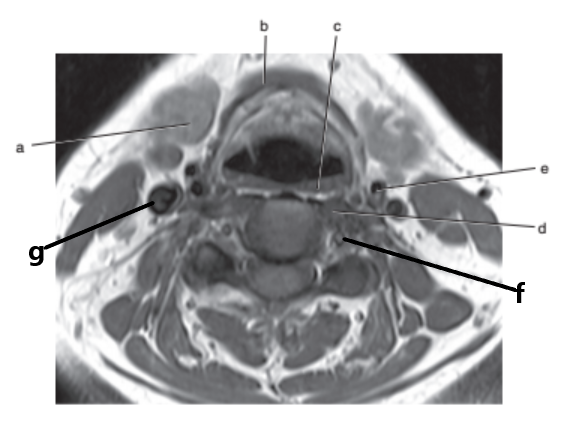

What is letter l ?

Common carotid

What is letter e ?

Subclavian artery

What is letter f ?

Common carotid artery

What anatomy is letter e ?

Nasopharynx

What is letter c ?

Sublingual gland

Vertebral artery

Sternocleidomastoid muscle

What is letter a ?

Submandibular gland

Parotid gland

Internal jugular vein

What is letter d ?

External carotid artery

Larynx

Spinal cord

What is letter h ?

What imaging plane is this ?

transverse

What anatomy is letter b ?

Epiglottis

Soft palate

Masseter muscle

Glottis

Mandible

Internal carotid artery

Hyoid bone

What is letter b ?

Cricoid cartilage